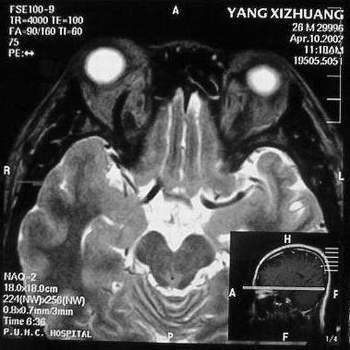

MRI及增强结果如下:

患者压颈及其它Valsava试验结果阴性。从MRI分析,在T1、T2、T+C检查该支血管均为明显流空现象,说明该血管血流速度很快,而从走行和分布看,眼上静脉可能性很大。也许也不能除外异常的眼动脉或异常血管。眶内主要可能的血管病变包括颈内动脉海绵窦瘘(高流窦)、AVM、眼眶静脉曲张、海绵状血管瘤、静脉性血管瘤、毛细血管瘤和眶内动脉瘤。。 1、颈内动脉海绵窦瘘:该患者临床有一部分支持该诊断。但从影像分析,海绵窦未见明显扩张;眼外肌未见明显充血扩张的长T1、长T2信号;颈内动脉海绵窦瘘常可见继发到血栓,可见到短T1、长T2的血栓信号。 2、眼眶静脉曲张:该疾患一般常见于小儿。该患大多数会出现Valsava试验阳性,间歇性突眼。不符合该患。影像学检查,于曲张静脉内常可见血栓和静脉石。所以不符合该患。 3、AVM:患者目前的影像学资料尚不全面,但可符合该诊断。临床上改病常见于30岁左右年轻人,单侧发病,于本患较符合。问题在于临床没有明确的血管杂音,似乎难以解释。 4、该患影像学与海绵状血管瘤差别很大,所以可基本排除此诊断。 5、静脉性血管瘤和毛细血管瘤:MRI中等T1、长T2信号,较易与本病鉴别。 6、眶内动脉瘤:我觉得患者并不能排除本病,但同样,由于波动性阴性,似乎也难以解释。 纵上所述:本人觉得,患者AVM可能性较大,同时不能除外眶内动脉瘤。 关于进一步检查,我觉得DSA价格过于昂贵。是否可先进行彩色多普勒检查,首先可以明确是静脉系统还是动静脉瘘抑或是动脉瘤。第二步,可进行MRA检查,可以清楚地显示海绵窦地相关关系,并可借此诊断或排除颈内动脉海绵窦瘘。如还需第三部检查,可进行MRV检查,对静脉系统进一步评价。三种检查总共的费用2000多圆,但给予我们的信息量已经很丰富了。 敬请各位医师提出自己的见解。 谢谢!